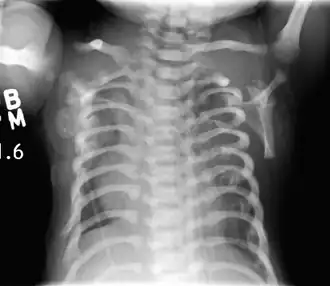

La distrofia torácica asfixiante (DTA), también llamada síndrome de Jeune, es una enfermedad hereditaria rara que se hereda según un patrón autosómico recesivo. Se incluye dentro del grupo de trastornos conocidos como osteocondrodisplasias por estar presente desde el nacimiento y afectar preferentemente al desarrollo de los huesos y cartílagos. La principal manifestación es un tórax estrecho y constreñido, lo que provoca insuficiencia respiratoria grave e infecciones pulmonares severas, otras manifestaciones son extremidades cortas, talla baja, anormalidades de la pelvis y los riñones. La mayor parte de los niños afectados mueren poco después del parto, aunque en algunas formas menos agresivas los pacientes tienen una expectativa de vida más larga. No existe tratamiento curativo, pero algunas técnicas quirúrgicas como la toracoplastia permiten mejorar los síntomas en ciertos casos. La distrofia torácica asfixiante es una de las enfermedades genéticas causadas por un mal funcionamiento del orgánulo intracelular denominado cilio primario, por ello se incluye dentro de las ciliopatías.[1][2]